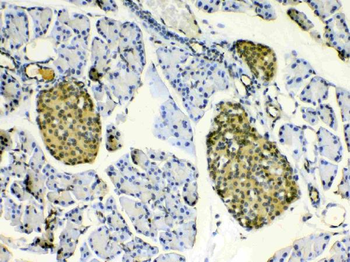

10 μg, 100 μg - Anti-PRDM1/Blimp1 Antibody [orb402200]

ELISA, IHC, WB

Human, Mouse, Rat

Rabbit

Polyclonal

Unconjugated

10 μg, 100 μg - Anti-Hsp90 alpha/HSP90AA1 Antibody [orb196259]